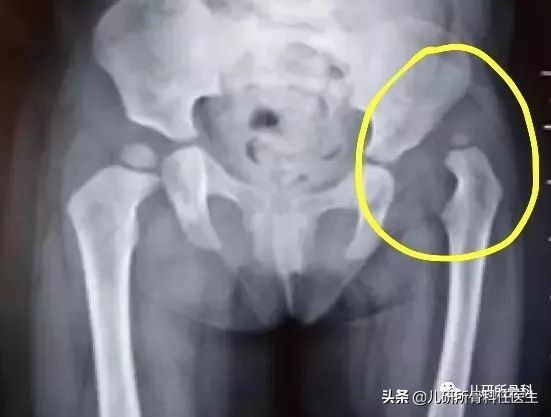

但是,在6个月以后,我们的股骨头最中间的地方会出现真正的骨组织,也叫骨化中心,它呢像一堵墙,会遮挡住超声波的来去,使超声波不能完成检查的任务。由于骨化中心是真正的骨组织,在X线片上可以显影,所以,6个月以上照X线片,结果会更准确。下图显示的是髋关节的X线片,圈内标记的就是脱位的髋关节。一旦发现这种情况,就需要进行专业的治疗了。